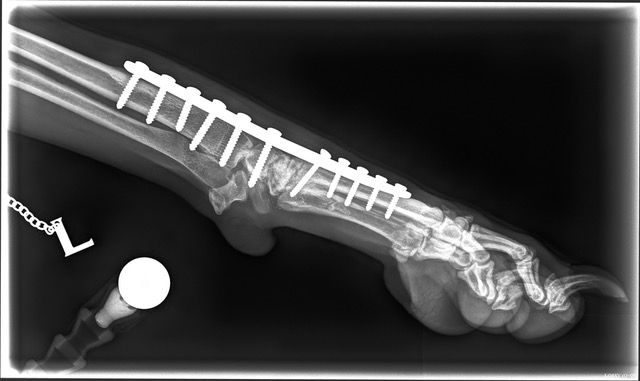

September 2021 - Unfortunately, Foxy had a traumatic accident on a walk, resulting in her totally rupturing the ligaments in her pastern (wrist) which are unrepairable, so she had to have surgery called a Pancarpal Arthrodesis to fuse the joints together and a plate put in her leg, culminating in an alteration to her gait and a low level permanent pain free lameness. (This injury is usually caused by either the dog running at speed and her leg going down a hole and then her twisting round, or by jumping from a great height and taking all the weight on her pasterns. In Foxy's case, it was likely to be the former.) She then spent 5 months in a crate with the level of exercise slowly increased until sufficient new bone had grown around the joints and after 5 months, she could start short off lead walks and thankfully is now back to her normal exercise levels. Obviously, this has now precluded her from being shown again which is extremely disappointing. However, Allan is hoping to continue to do some light Gundog work with her and hopefully enter some working tests.

The photos below show the metalwork in her leg but she lives a perfectly normal life and is back to her happy, outgoing self, which is the best possible outcome for our fabulous Foxy.